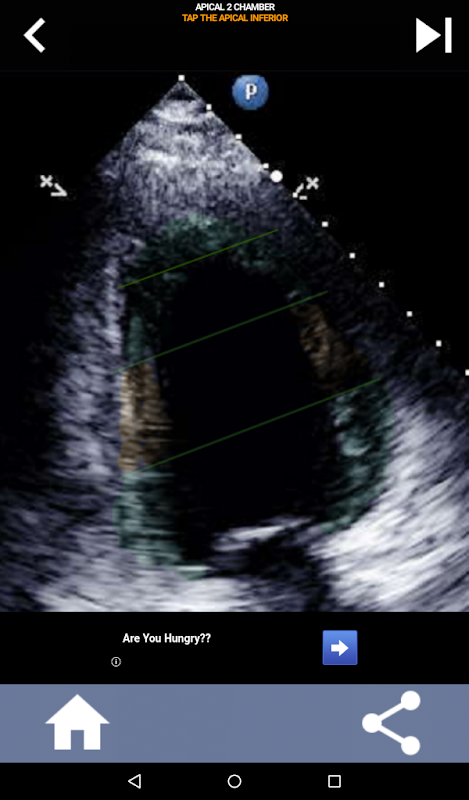

نهج مرئي قائم على الاختبار لتعلم قطاعات القلب AHA: تخطيط صدى القلب

يعد فهم قطاعات القلب من جمعية القلب الأمريكية (AHA) أمرًا في غاية الأهمية بالنسبة لأخصائي تخطيط الصدى القلبي للتواصل بشكل فعال مع طبيب القلب الذي يكتب التقرير. من خلال معرفة المناطق التشريحية المحددة والقطاعات المقابلة لها ، يمكن لأخصائي الموجات فوق الصوتية أن يصف بدقة أي تشوهات أو نتائج ونقلها ، مما يضمن التواصل الواضح والموجز بين كلا المهنيين.

يصبح هذا الفهم حاسمًا بشكل خاص عندما يسعى طبيب القلب إلى التأكد من الموقع الدقيق للمشكلة أو عندما يحدد الطبيب عند الطلب مشكلة داخل منطقة معينة ، مما يدفع أخصائي الموجات فوق الصوتية لعرض المقطع المقابل بدقة ، مثل الجدار الأوسط السفلي. وبالتالي ، فإن امتلاك فهم شامل لمقاطع القلب AHA هو مجموعة مهارات أساسية.

سيختبر هذا التطبيق معرفتك باستخدام صور صدى فعلية ، والتي أجدها غالبًا أفضل طريقة تدريس.